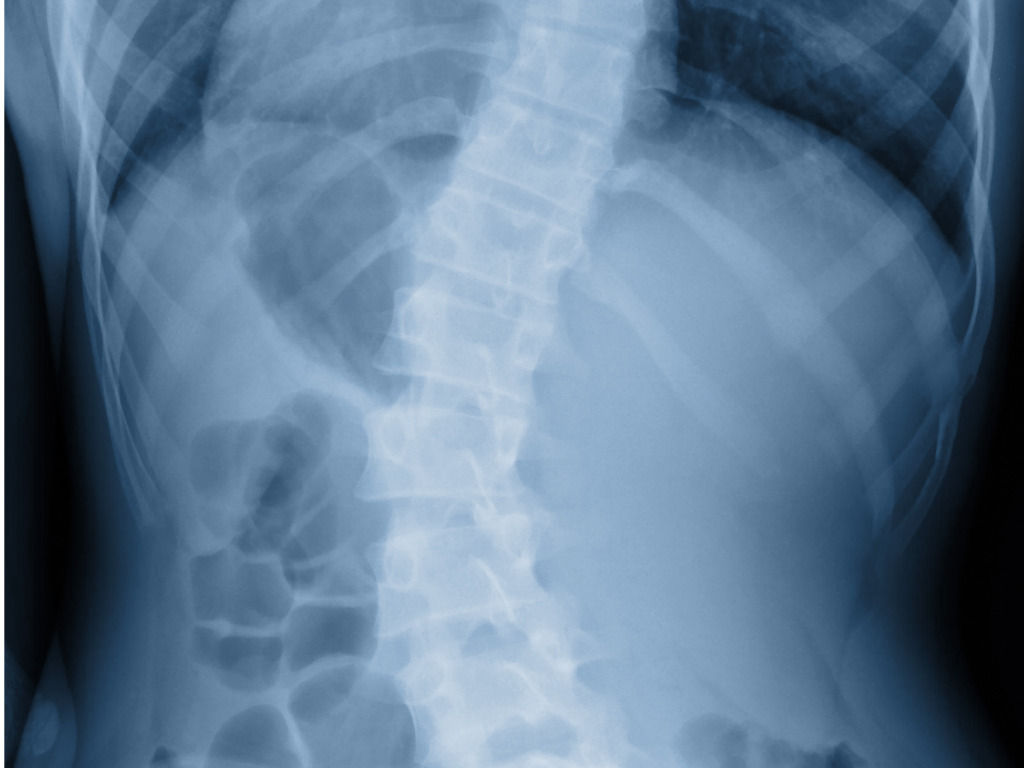

A escoliose é a forma de deformidade espinhal mais conhecida em nosso meio. Nos pacientes em que não se pode encontrar a causa da escoliose (até 85% dos casos),…